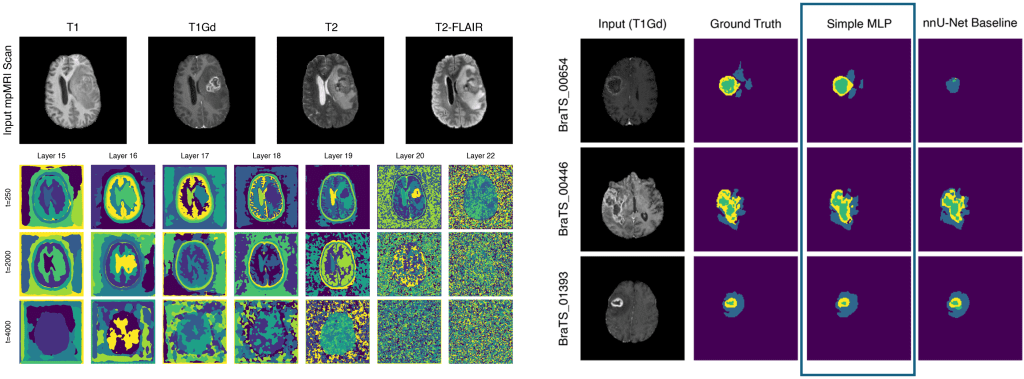

Der Erfolg von Machine-Learning-Methoden hängt allerdings von der Qualität und Anzahl der Trainingsdaten ab. Gerade in der Medizin fehlen oft Daten mit „Ground Truth“, oder sie stehen aus Datenschutzgründen nicht zur Verfügung. Deshalb arbeitet das Team an Methoden zur vereinfachten, interaktiven Erstellung von Ground Truth. Dazu zählen z. B. CycleGANs zum Generieren synthetischer Trainingsdaten, One-Shot Learning zur Datenaugmentierung, Transfer Learning zur Wiederverwendung bestehender Wissensmodelle sowie Domain Adaptation zur Anpassung an neue Datenverteilungen.

Gelernte visuelle Repräsentationen des BRATS Datensatzes für ein Diffusionsmodell (links) und daraus abgeleitete Segmentierungen eines Gehirntumors für nur zehn Trainingsbilder (rechts).

Learned Visual Representations of the BRATS dataset from Diffusion (left) and derived segmentations for only ten training slices (right).